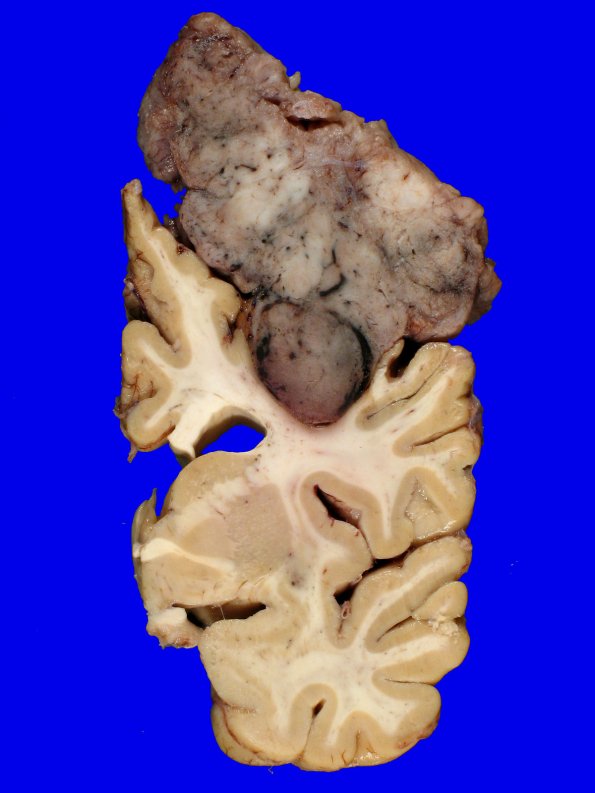

Washington University Experience | NEOPLASMS (MENINGIOMA) | Gross Pathology | 72D7 NCL (Case 72) Gross_17

Additional images of the tumor relationship with the brain.